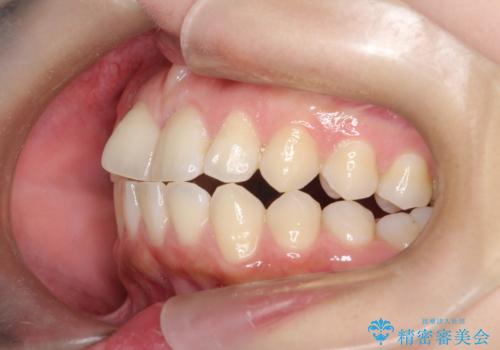

右下第二小臼歯の舌側転移の改善

- 患者様は、右下第二小臼歯が舌側に転移していることが主訴でした。診断の結果、抜歯を伴う矯正治療も検討しましたが、奥歯の遠心移動とIPR(インタープロキシマルリダクション)を行うことで、非抜歯で矯正を進めることが可能であると判断しました。治療計画では、審美ワイヤーを用いた2年間の治療で、歯列を整えつつ、臼歯関係や正中のバランスを維持しながら進めました。

非抜歯矯正では、歯の動きを慎重に調整することが求められます。本症例では、奥歯を遠心に移動させることで、舌側に転移した右下第二小臼歯の位置を改善しました。また、IPRを行うことで歯間スペースを確保し、無理なく歯列の調整を行いました。非抜歯での治療は、特に臼歯関係や正中を保ちながら治療できるというメリットがあり、最終的にはバランスの取れた歯並びを実現できました。審美ワイヤーを使用したことで、治療中も目立ちにくく、患者様の見た目にも配慮した治療を行いました。